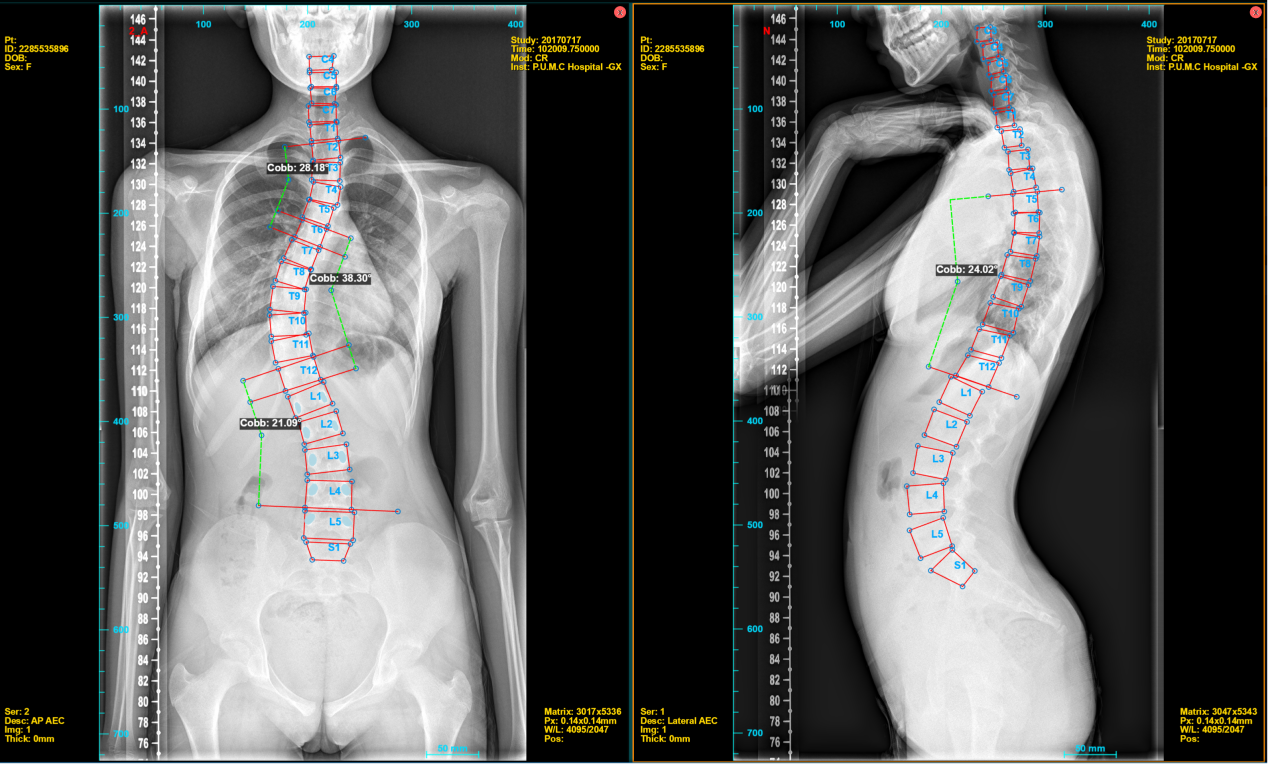

子課題四《脊柱畸形智能影像評估及術前規劃新產品研發》中,德康醫療共同開發的“脊柱畸形多維度高清成像評估系統”客戶端已具備椎體關鍵點自動檢測、COBB角自動測量、LENKE分型判定、AI手術規劃等功能,并規劃納入子課題六《新產品和系統的前瞻性、多中心臨床評價及驗證》開展多中心臨床研究,目前已收集數百例患者的病歷及影像學資料并納入系統進行驗證研究。